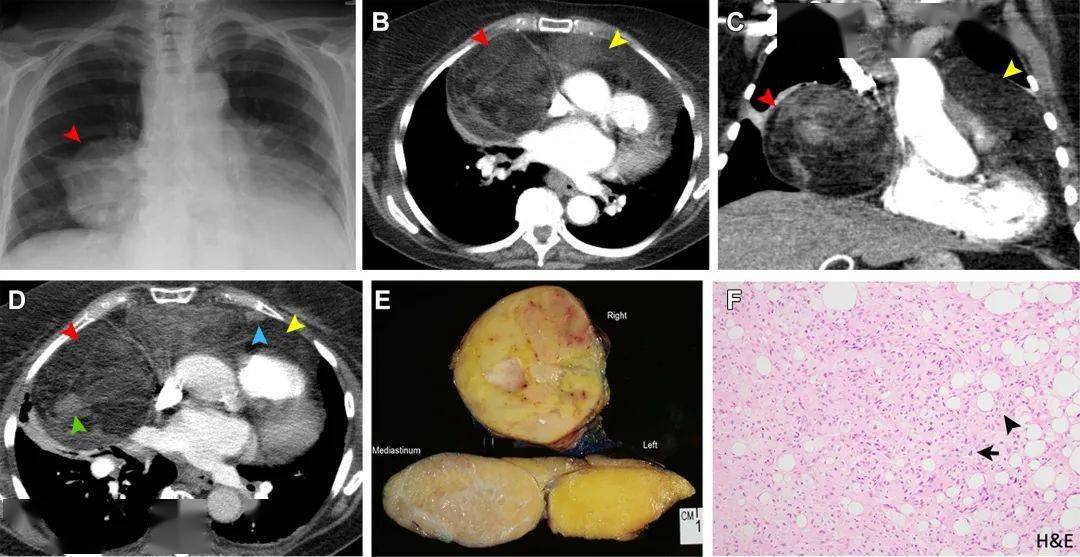

罕见原发性纵隔脂肪肉瘤6例影像及临床表现

纵隔髓脂肪瘤影像诊断